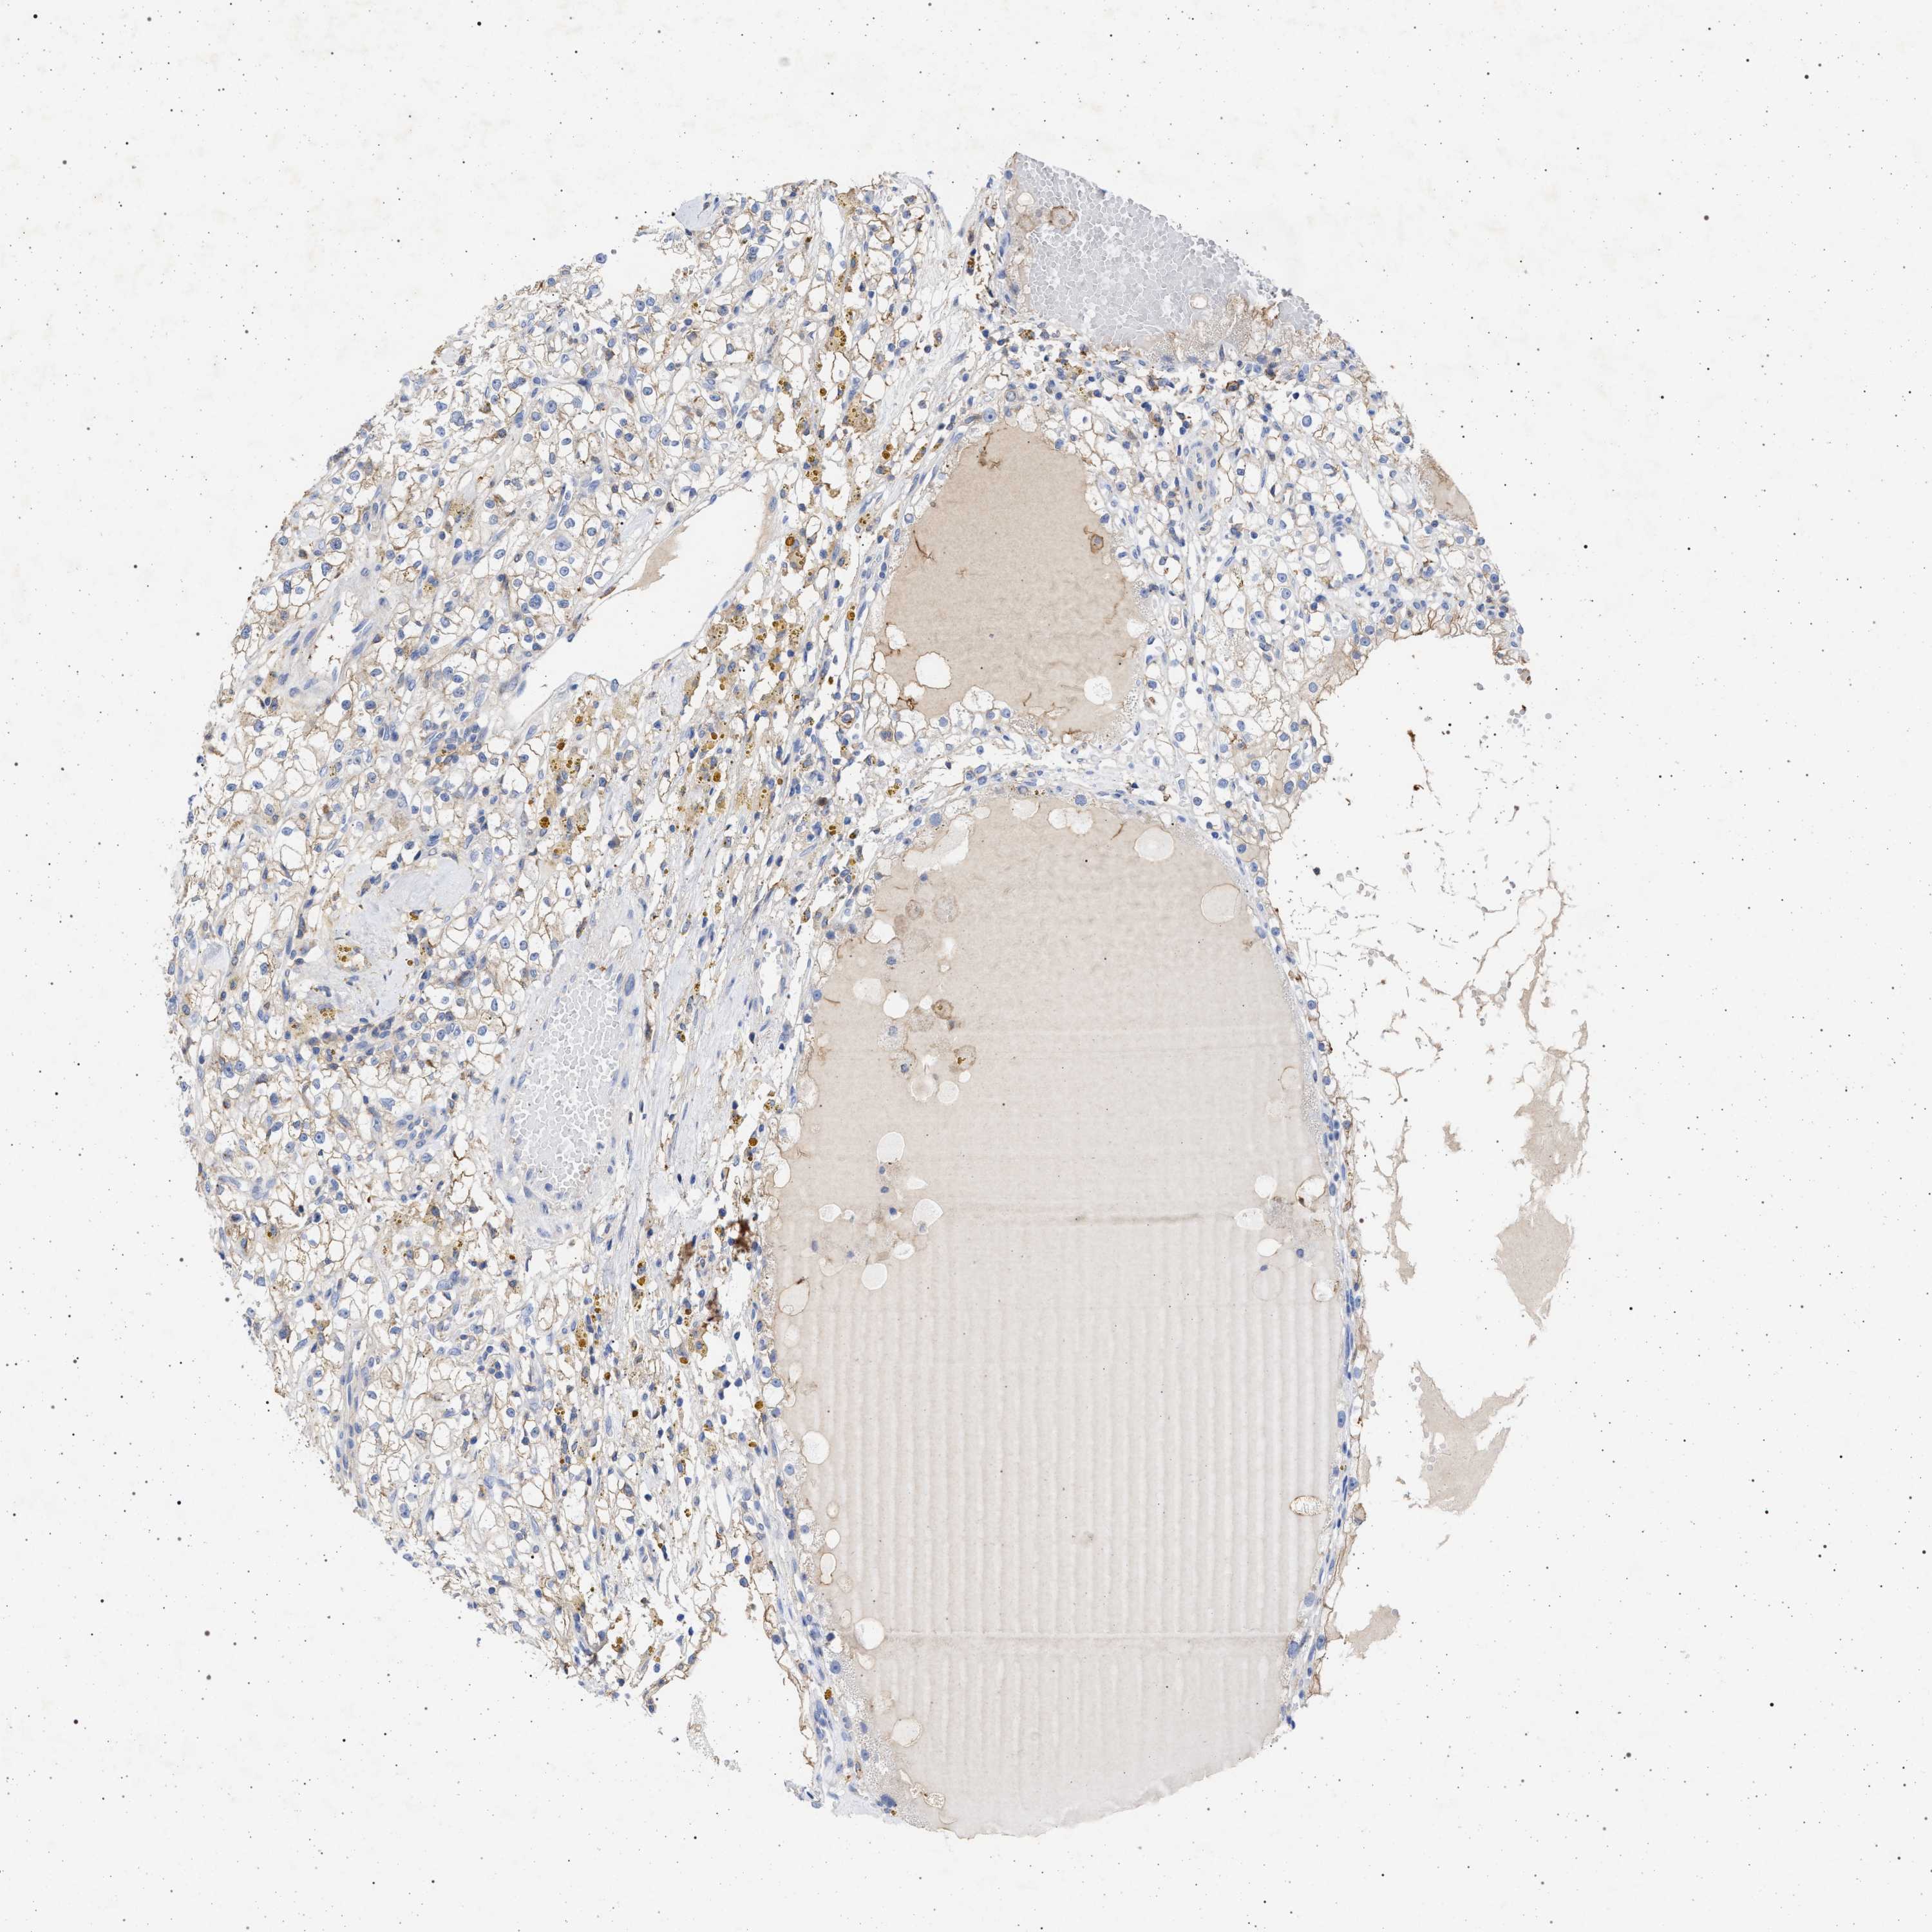

KIDNEY RENAL CLEAR CELL CARCINOMA (VALIDATION) - Interactive survival scatter ploti

The Survival Scatter plot shows the clinical status (i.e. dead or alive) for all individuals in the patient cohort, based on the same data that underlies the corresponding Kaplan-Meier plots. Patients that are alive at last time for follow-up are shown in blue and patients who have died during the study are shown in red.

The x-axis shows the expression levels (FPKM) of the investigated gene in the tumor tissue at the time of diagnosis. The y-axis shows the follow-up time after diagnosis (years). Both axes are complimented with kernel density curves demonstrating the data density over the axes. The top density plot shows the expression levels (FPKM) distribution among dead (red) and alive patients (blue). The right density plot shows the data density of the survived years of dead patients with high and low expression levels respectively, stratified using the cutoff indicated by the vertical dashed line through the Survival Scatter plot. This cutoff is automatically defined based on the FPKM cutoff that minimizes the p-score. The cutoff can be changed by dragging the vertical line or by entering a cutoff value in the square labeled "Current cut-off".

Under the Survival Scatter plot the p-score landscape (black curve; left axis) is shown together with dead median separation (red curve; right axis). Dead median separation is the difference in median mRNA expression between patients who have died with high and low expression, respectively. It is calculated as follows: median FPKM expression of dead patients with high expression - median FPKM expression of dead patients with low expression. This is intended to aid the user in visually exploring custom cutoffs and the associated p-scores and dead median separation.

Individual patient data is displayed and can be filtered by clicking on one or more of the category buttons on the top of the page. Categories describing expression level and patient information include: high, low, alive, dead, female, male and tumor stages. The scale of the x-axis can be toggled between linear and log-scale by clicking on the "x log" button. Mouse-over function shows TCGA ID, patient information and mRNA expression (FPKM) for each patient.

& Survival analysisi

Kaplan-Meier plots summarize results from analysis of correlation between mRNA expression level and patient survival. Patients were divided based on level of expression into one of the two groups "low" (under cut off) or "high" (over cut off). X-axis shows time for survival (years) and y-axis shows the probability of survival, where 1.0 corresponds to 100 percent.

PLG is not prognostic in Kidney Renal Clear Cell Carcinoma (validation)

Best expression cut offi

Based on the FPKM value of each gene, patients were classified into two groups and association between prognosis (survival) and gene expression (FPKM) was examined. The best expression cut-off refers the FPKM value that yields maximal difference with regard to survival between the two groups at the lowest log-rank P-value. Best expression cut-off was selected based on survival analysis .

When clicking on this number, the vertical dashed line indicating cut-off, the interactive survival plot, and the Kaplan-Meier curve will be adjusted to show results based on the best expression cut-off.

: 0.86

TCGA RNA samplesi

RNA-seq data is reported as average FPKM (number Fragments Per Kilobase of exon per Million reads), generated by the The Cancer Genome Atlas (TCGA) .

Normal distribution across the dataset is visualized with box plots, shown as median and 25th and 75th percentiles. Points are displayed as outliers if they are above or below 1.5 times the interquartile range. FPKM values of the individual samples are presented next to the box plot.

Average pTPM 15.6

Number of samples 100